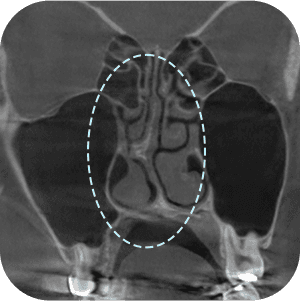

The implant information from the previous surgery is checked

Functional problems such as a deviated septum are checked for

The current implant location is checked

Nasal CT scan, is it necessary?

ASince this is a revision surgery,

a more precise diagnosis is a must!

external appearance and internal functional

problems of the nose are accurately

diagnosed through 3D-CT.